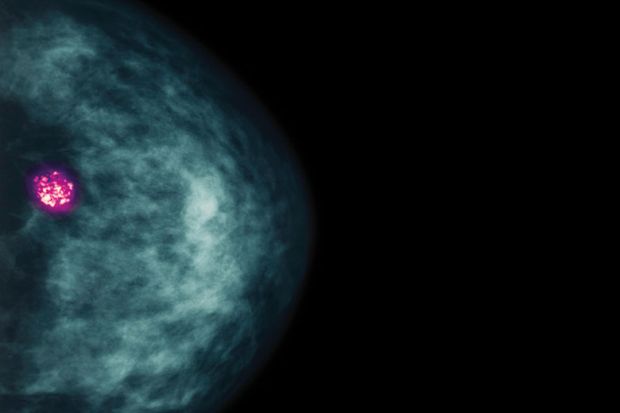

Thanks to advances in genome sequencing, medical imaging and other technologies, we now have a deeper understanding of many cancers than we could have imagined. What’s more, this understanding is resulting in smarter therapies that are directly benefiting patients. For example, radiotherapy can cure more than 90 per cent of localised prostate cancers. The i-Knife, a novel surgical device, “smells” tumour cells and guides the surgeon to remove more of the tumour and spare the healthy tissue. Meanwhile, radiotherapists are developing the MR-Linac, an integrated device that will take images of the patient and adjust the therapeutic radiation beam in real time to focus on the tumour and avoid healthy organs.

But mathematical modelling and artificial intelligence offer the prospect of analysing data from genomics, pathology and clinical imaging together, looking for hidden signals in these vast data. This could map the complex molecular communication networks used by cancer genes, identify novel drug targets and discover uses for already approved drugs outside their initial indications. AI is also helping us to map a better collective view of the patient, allowing us, for example, to better predict the risk of side-effects, informing clinicians to help them plan therapy. Importantly, AI will play a pivotal role in early detection of cancer, and the US Food and Drug Administration has approved the first AI-based software for tracking cancer.